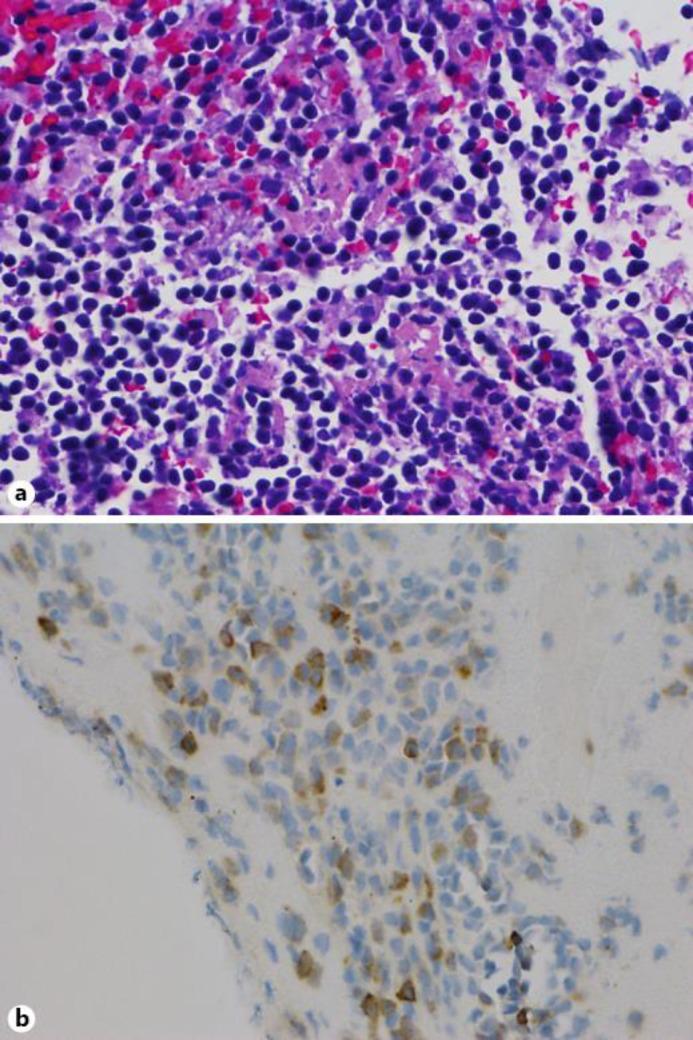

In this case report and review of the literature, we describe a particularly unusual case of a 25-year-old man who presented to our hospital with bilateral exudative retinal detachments associated with posterior pole thickening without any hematological or neurological findings. The patient, who had a history of previously treated pre-T-ALL in complete remission, was found to have leukemia cell infiltration on retinal biopsy.